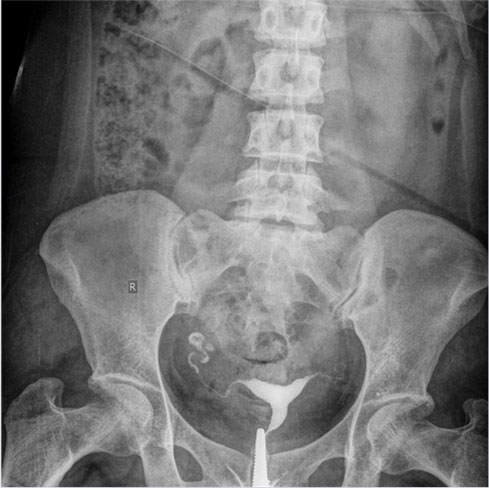

An Intravenous Pyelogram (IVP) or Intro Venous Urogram is a special X-Ray examination of Kidneys, Bladder & Ureters.

For an intravenous pyelogram, an intravenous line will be put in your arm or hand. A dye ( contrast material ) is injected into a vein. An IVP usually takes less than 1 hour. If your kidneys work more slowly, the test can last up to 4 hours or as required.